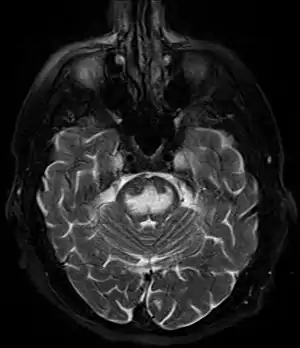

Pode ser diagnosticado clinicamente no contexto apropriado, mas pode ser difícil de confirmar radiologicamente usando técnicas de imagem convencionais. As alterações são mais proeminentes na ressonância magnética (RM) do que na tomografia computadorizada (TC), mas geralmente levam dias ou semanas após o início dos sintomas agudos. A imagem por RM normalmente demonstra áreas de hiperintensidade em imagens ponderadas em T2.[29]